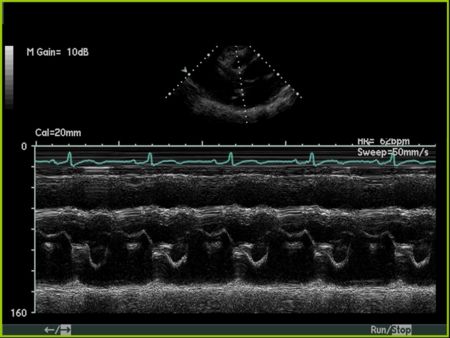

M Mode in Mitral Stenosis

- Leaflet tips bright (calcified) and thickened

- E/F slope decreased